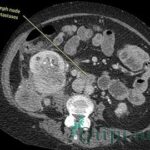

В зависимости от факторов производят рентген грудного отдела или позвоночного столба, проводится МРТ, снимается кардиограмма, сердце исследуют ультразвуком. Если факторы, вызвавшие боли кроются в заболеваниях ЖКТ, то пациенту предлагают пройти фиброгастродуоденоскопию. Если причиной послужили патологии органов дыхания, то врачами производится бронхоскопия. Дополнительно пациентом сдаётся ряд анализов: моча, кал, кровь и т. д.